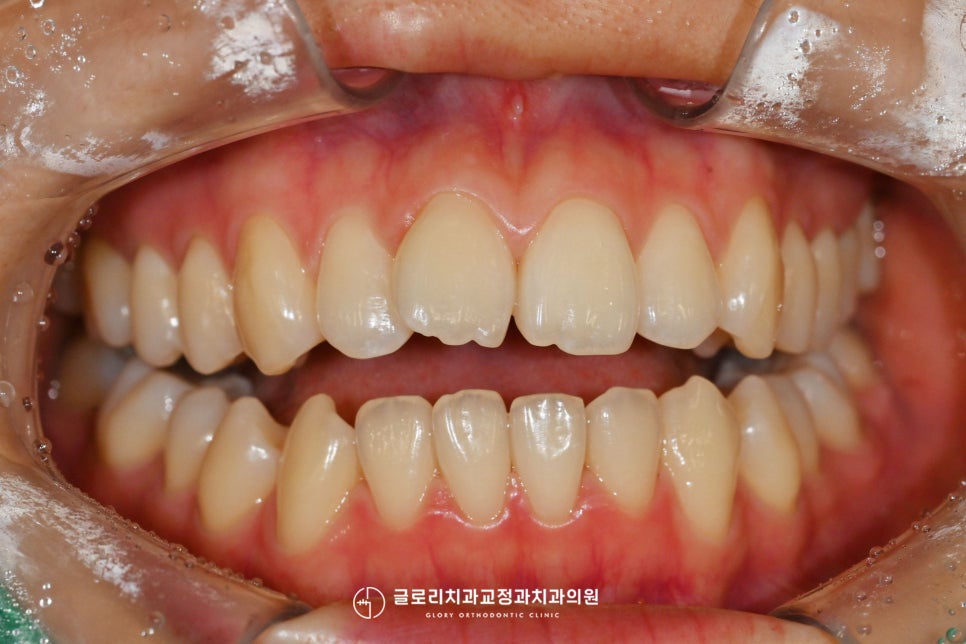

정면에서 구내를 보았을 때

위 전치부의 틀어짐이 관찰되는데요.

크게 회전된 양상은 아니었지만,

정중선이 일직선으로 맞지 않아

조금 눈에 띄는 정도였는데요.

이렇게 전치부가 틀어졌거나

살짝 불규칙한 느낌이 드는 경우에는

주로 앞니 부분교정을 시행합니다.